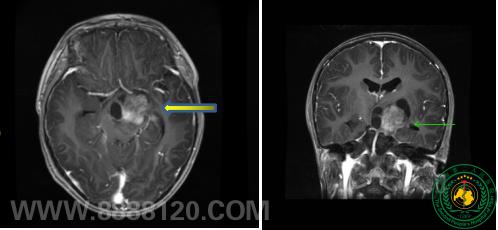

手脚乏力需重视,警惕颅内肿瘤作怪

手脚乏力需重视,警惕颅内肿瘤作怪26272